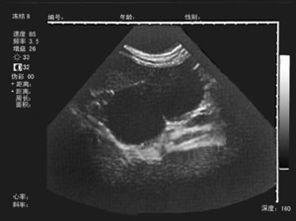

4卵泡囊肿

卵泡囊肿的母猪主要表现为持续的发情症状,外阴红肿,流大量的稀薄粘液。